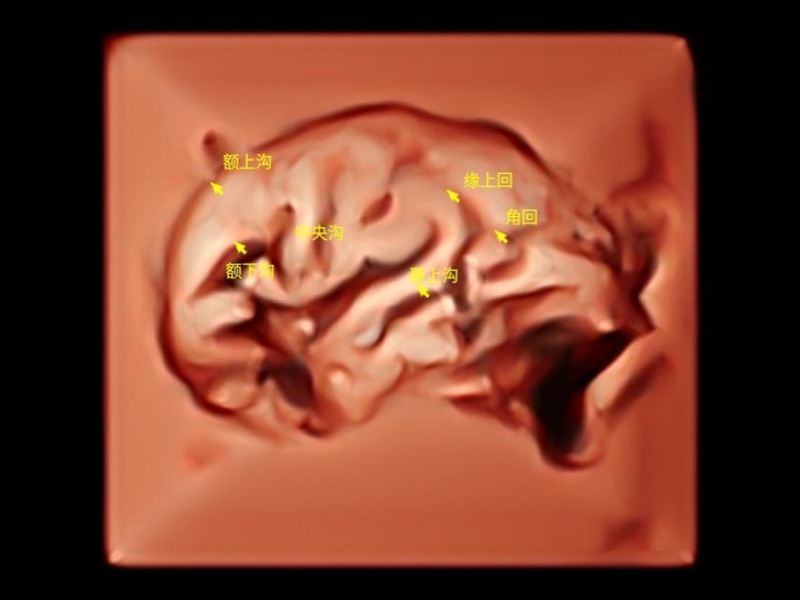

在傳統(tǒng)血流的基礎(chǔ)上優(yōu)化掃查和算法策略,能夠更好的抑制組織信息,提煉紅細(xì)胞運(yùn)動(dòng)信息,得到更高幀頻,高靈敏度和分辨率的血流信號(hào),還原更真實(shí)的血流動(dòng)力學(xué)。

通過(guò)光照模型,使二維血流顯示出立體的效果,增加血流的敏感性、成束性,減少外溢。可以和其他不同的血流技術(shù)聯(lián)合使用,融合不同技術(shù)的優(yōu)勢(shì)。輕松應(yīng)對(duì)微小血管,增強(qiáng)血流的立體效果,提升視覺(jué)敏感性。

通過(guò)創(chuàng)新的Matrix E自適應(yīng)濾波算法,能有效濾除軟組織和噪聲信號(hào),最大限度保留超低速微細(xì)血流的信號(hào);結(jié)合超長(zhǎng)時(shí)間域算法,極大提升細(xì)微血流的敏感性和空間分辨率,更真實(shí)的反應(yīng)組織、包塊的血流灌注情況。